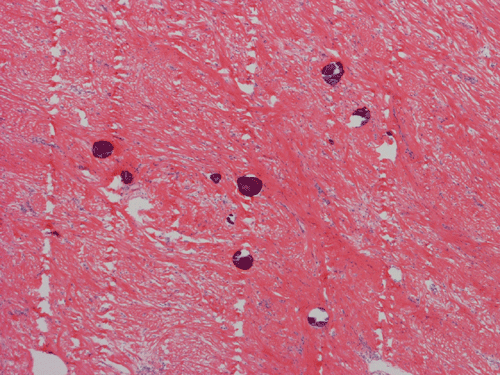

Pathology of the Case: Macroscopically, the nodules are well circumscribed, irregular, and stone hard. The cut surface is solid, gray-white, and free of necrosis. An intraoperative frozen section was performed to rule out metastatic carcinoma, Hodgkin's and non-Hodgkin's lymphoma, and sarcoma. Histologically, the material submitted for frozen section demonstrated hyalinized, hypocellular fibrous tissue with large, calcified nodules (Panel A and B). The section submitted for frozen sections was similar. The bulk of the specimen is composed of hypocellular, hyalinized collagenous tissue with occasional small irregular islands of chronic inflammatory cells (Panel C and D). The nuclei does not display significant nuclear atypia (Panel E). Many large psammoma bodies (Panel F and G)  are present and they are not associated with inflammatory cells. There are also extensive areas with no evidence of either calcifying nodules or inflammatory cells (Panel H). A segment of colon was also resected and the pathology is consistent with Crohn's disease.

Calcifying fibrous tumors are often well circumscribed, firm masses most commonly ranging in size from 1 to 4 cm in greatest dimension. However, the lesions can reach up to 15 cm.  Microscopically, the tumor is a well circumscribed mass showing diffuse hyalinization and benign appearing spindle cells intermixed with a prominent chronic inflammatory infiltrate. The inflammatory component is composed mainly of lymphocytes, eosinophils, and mast cells.  There is usually no hypercellular areas, significant atypia, or mitotic activity. Necrosis and hemorrhage are not seen. This lesion is not infiltrative. As the name implies, a hallmark of the lesion is the presence of calcifications, which may be psammomatous or dystrophic and are sometimes associated with foreign body type giant cell reaction.  It is believed these lesions are reactive because there is no documented evidence of cytogenetic or molecular disruptions that may suggest clonality 8